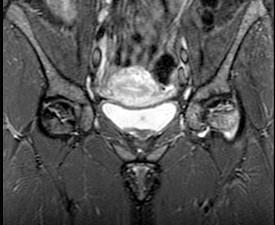

问题 女,34岁,双侧髋部疼痛,结合图像,最可能的诊断是 ( )

选项 A、股骨头缺血坏死 B、痛风 C、类风湿关节炎 D、髋关节退行性变 E、未见异常

答案 A